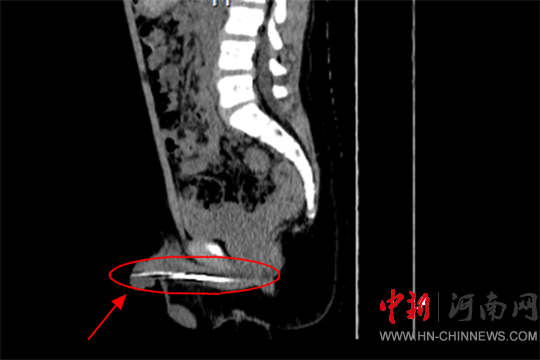

經(jīng)過詳細(xì)檢查

確認(rèn)鋼針大概8-9公分

卡在了尿道內(nèi)

且伴有嚴(yán)重的出血